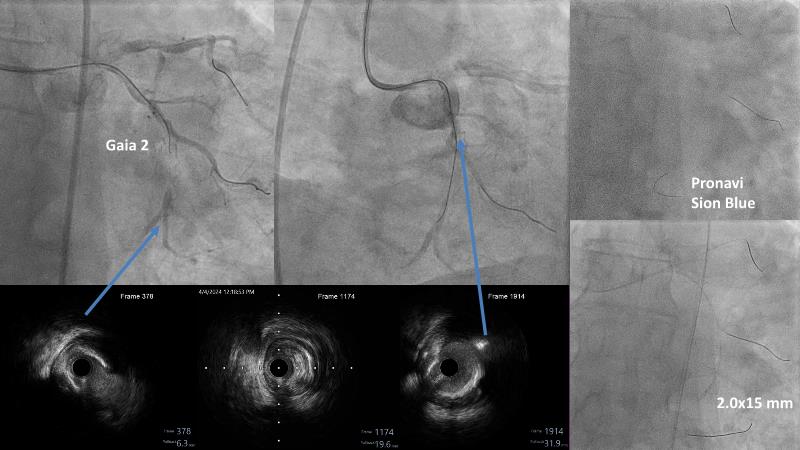

Don't miss this session for expert guidance on preparing and managing complex lesions. Gain insights into choosing the right tools, including microcatheters and balloons, for optimal treatment outcomes. Explore the innovative features of flagship devices for complex PCI, and Pronavi microcatheter and Alveo HP CTO balloon to treat complex CTO lesions. Learn about the safety and efficacy of the Wedge NC scoring balloon, the importance of using POT dedicated balloons in POT and DOT techniques, and get updated tips and tricks from ongoing clinical practices.

- To know the innovative features and capabilities of flagship devices in advancing complex PCI treatment

- To gain insights on Pronavi microcatheter and Alveo HP CTO balloon to treat complex CTO lesions, understand the safety and efficacy of lesion preparation with Wedge NC scoring balloon and the significance of using POT dedicated balloon in POT and DOT technique